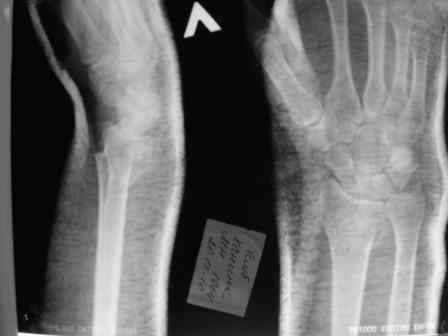

Уважаемые коллеги.Прошу обсудить случай лечения перелома дистального метаэпифиза лучевой кости. Ситуация скандальная и крайне неблагоприятная. Больная с патологической обстоятельностью мышления, склонностью к сутяжничеству, патологическими умозаключениями, не поддающимися коррекции (см. психиатрию, правда офиц. диагноза нет). В данном случае есть ряд ошибок с нашей стороны, прежде всего в отношении качества ведения документации (за что получил административное взыскание, по делом мне дураку). В остальном- придерживались в лечении подхода классический советской школы. Так как умную операцию…… сами знаете… 15.12- перелом луча в Москве. Там же репозиция, гипс. Дальнейшее лечение у нас в ЦРБ. 20.12.- вторичное смещение в гипсе21.12- под внутривенным наркозом- репозиция, гипсовая лонгета. Дальше начинается самое интересное. После репозиции больная заявила, что я (репозицию делал я) порвал ей все связки в суставе, посинел у нее 5 палец, якобы я за него тянул и т. д. На самом деле на 2 сутки после репозиции рука немного отекла и было незначительное сдавление гипсом, который был ослаблен. Дальнейшее лечение консервативное. Через 6 недель- гипс снят, назначено ЛФК. Пациентка крайне недовольна. Говорит, что на снимке у нее выступает кость, я ей сломал руку и.т.д. В общем началось. Пациентка прочитала в интернете наверное все, что есть по данной травме.По заключениями рентгенологов и консультанта из КДЦ областной больницы - стояние отломков допустимое. Объективно говоря- снижена высота лучевой кости, диастаз лучелоктевого сочленения, и не сросся шиловидный отросток. однако на РКТ при сравнении с другой стороной- разница незначительная. Дальше в одной из больниц нашей области и одной из больниц Москвы (вроде бы КГБ 53) врачи сказали, что репозиция сделана плохо. Нужна операция (восстановить длину лучевой кости), даже один из них предложил РЕДРЕССАЦИЮ (хи-хи) с наложением аппарата Илизарова. Что это для данной больной- радость неописанная. (см. описание психического статуса). Ничем другим, кроме зарабатывания дешевого авторитета объяснить данный факт не могу.Кстати, у больной еще нейропатия локтевого нерва.Для разрешения конфликта больная направлена на консультацию в ЦИТО на 03.03.11.

Теперь вопросы: 1.Прошу объективно оценить качество нашей репозиции на момент 21.12. (неужели так плохо?). Что на снимках при снятии гипса- сам вижу. 2. сравнить снимки РКТ (с двух сторон)- так ли велико укорочение лучевой кости и лучелоктевой диастаз. 3. Ваши мнения, в отношении целесообразности оперативного лечения учитывая ВСЕ вышеизложенное. 4. На всякий случай для суда- мог ли я тракцией в 2- 3 кг за 1 и 2 пальцы под внутривенным наркозом неправильно вколотить отломки и травмировать локтевой нерв. Кстати, в США если врач пациенту говорит, что его плохо лечили- то этого врача лишают лицензии. У нас наооборот- обгадить другого милое дело. И это процветает. От себя же могу сказать, что никто в нашем отделении так не поступает. Коллеги, будьте осторожны в своих высказываниях. От осложнений и ошибок никто не застрахован. А в данном случае многое будет зависеть от заключения консультантов поликлиники ЦИТО, куда больная направлена областным травматологом на 03.03 для решения вопроса о дальнейшей тактики лечения. С уважением ко всему травматологическому сообществу Дедок Михаил.

1. РЕПОЗИЦИЯ сделана качественно(ОСНОВНЫЕ 2 УГЛА ВЫСТАВЛЕНЫ ПРАВИЛЬНО ) , но перелом нестабильный и склонен к втор смещению . Поэтому мы стараемся все переломы со смещением фиксировать 3-МЯ спицами по GRIN методике .

1. Репозиция от 21.12.10 была выполнена лучше, чем первичная.